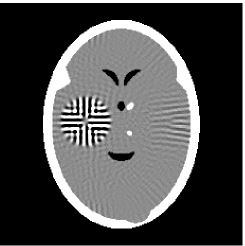

Furthermore, we used the classic ART iteration as the iteration operator in our numerical experiments. In order to compare the proposed superiorization algorithm with the classic superiorization algorithm, we applied the classic superiorization and -PP superiorization algorithm to two phantoms (see figure 1). The first one is the Shepp-Logan phantom[30], and the second one is the head phantom with a ghost which is invisible at 22 specified projection directions [10, 31]. In addition, we compare the performances of the two algorithms for the noiseless and noised data with different projections. In all experiments, the noised projection data was corrupted by additive Gaussian white noise with variance . We record the iterations, running time of program and mean square error (MSE) of different algorithms, where MSE is computed by

Noiseless projection data: Since the ghost in this phantom is invisible at 22 directions [10, 11], the reconstruction images usually suffer from artifacts. in our simulations, the projection data were collected in 112 and 82 directions: 90 and 60 with equal angle increments from to and 22 specified views in which the ghost is invisible [10]. Iteration procedures were terminated when for the noiseless projections.

The reconstruction images from the noiseless projection data were shown in the Fig. 6. For comparison, Table 3 present the iterations, MSE, Res and running time(RT) of different reconstruction results.

Noised projection data: For the noised projection data, the iteration processes were terminated when for 82 and 112 projections. The reconstruction images were given in Fig. 7. Table 4 showed the MSEs, iterations and running time of program of the results of images in Fig. 7.